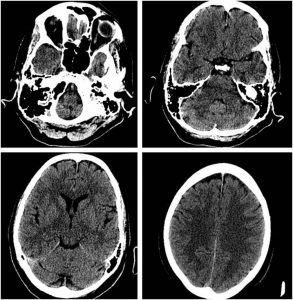

TC de urgencias. Normal, sin hallazgos patológicos relevantes.

Descripción:TC. Tc craneal sin contraste sin hallazgos patológicos valorables a nivel infra ni supratentorial.